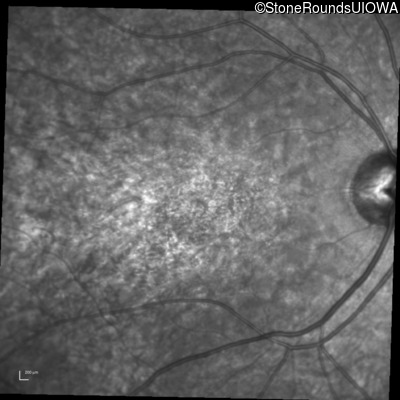

Infrared Fundus Photograph - Right - 20/50 +2

Exemplar